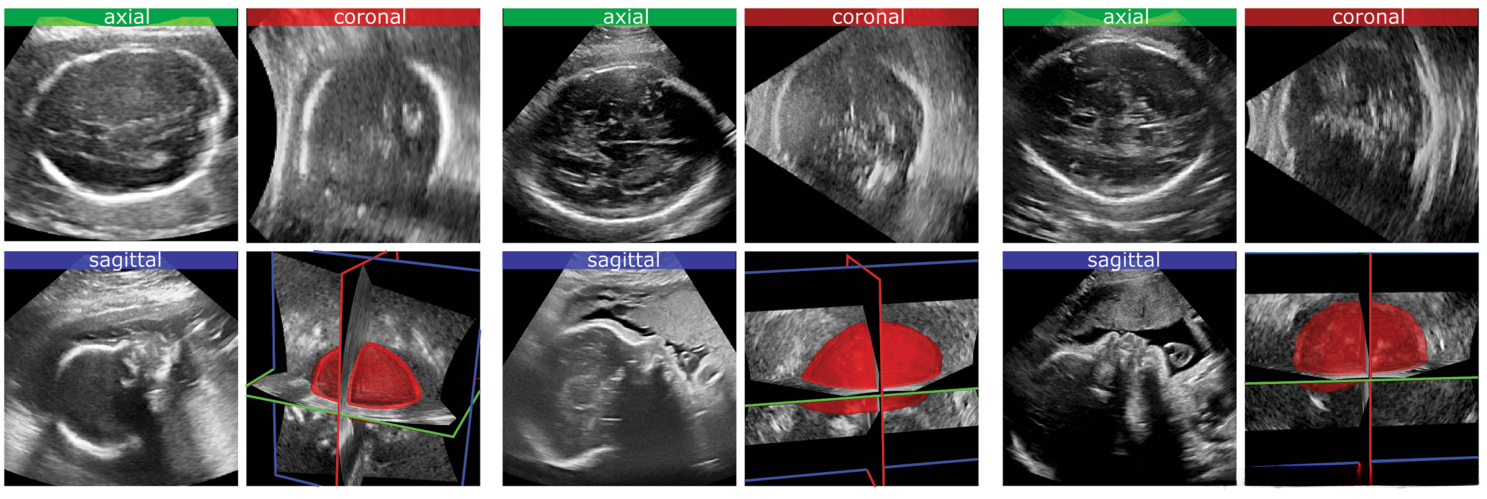

图1展示了胎儿头部的标准化超声图像。包括三种标准切面:轴位(绿色)、矢状位(蓝色)和冠状位(红色)。此图像显示了从相应三维超声体积中手动分割出的颅骨三维结构的清晰呈现。

数据预处理:采用非局部均值滤波方法对手据进行预处理,并按每维0.50毫米的空间分辨率进行重新采样;将D体积设定为96×96×96体素大小、2D标准平面设定为96×96像素大小;必要时可借助裁剪技术和零填充方法来实现。标准平面对齐方式不做要求,在配置时可以选择镜像或翻转变换策略(例如图1所示的近似定位集合)